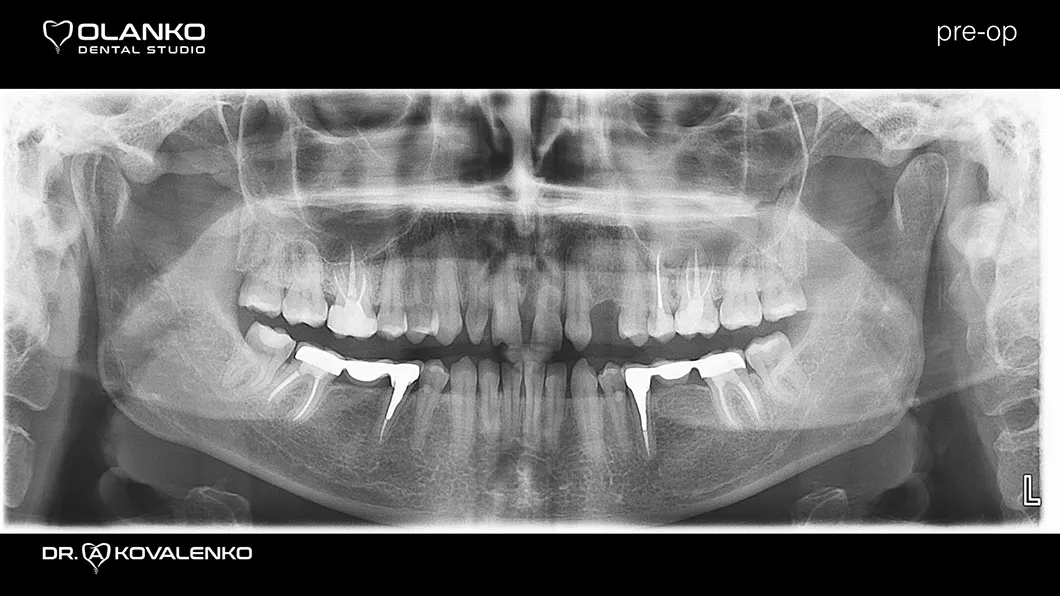

Клинический случай 3 протезирование

Пациентка обратилась с жалобами на неудовлетворительную эстетику, наличие промежутков между зубами (тремы, диастемы) полное отсутствие (адентия бокового резца слева).

Диагностика: эстетический анализ, создание проекта новой улыбки DSD (цифровой дизайн улыбки).

Лечение: замена старых несостоятельных композитных реставраций и лечение кариеса, повторное лечение каналов с использованием микроскопа в 3х зубах.

Установлен зубной имплантат в области 23 зуба.

Проведена хирургическая коррекция десневого контура в области фронтальных зубов.

Протезирование:12 керамических реставраций (коронки,виниры на зубах и имплантате) на верхней челюсти.